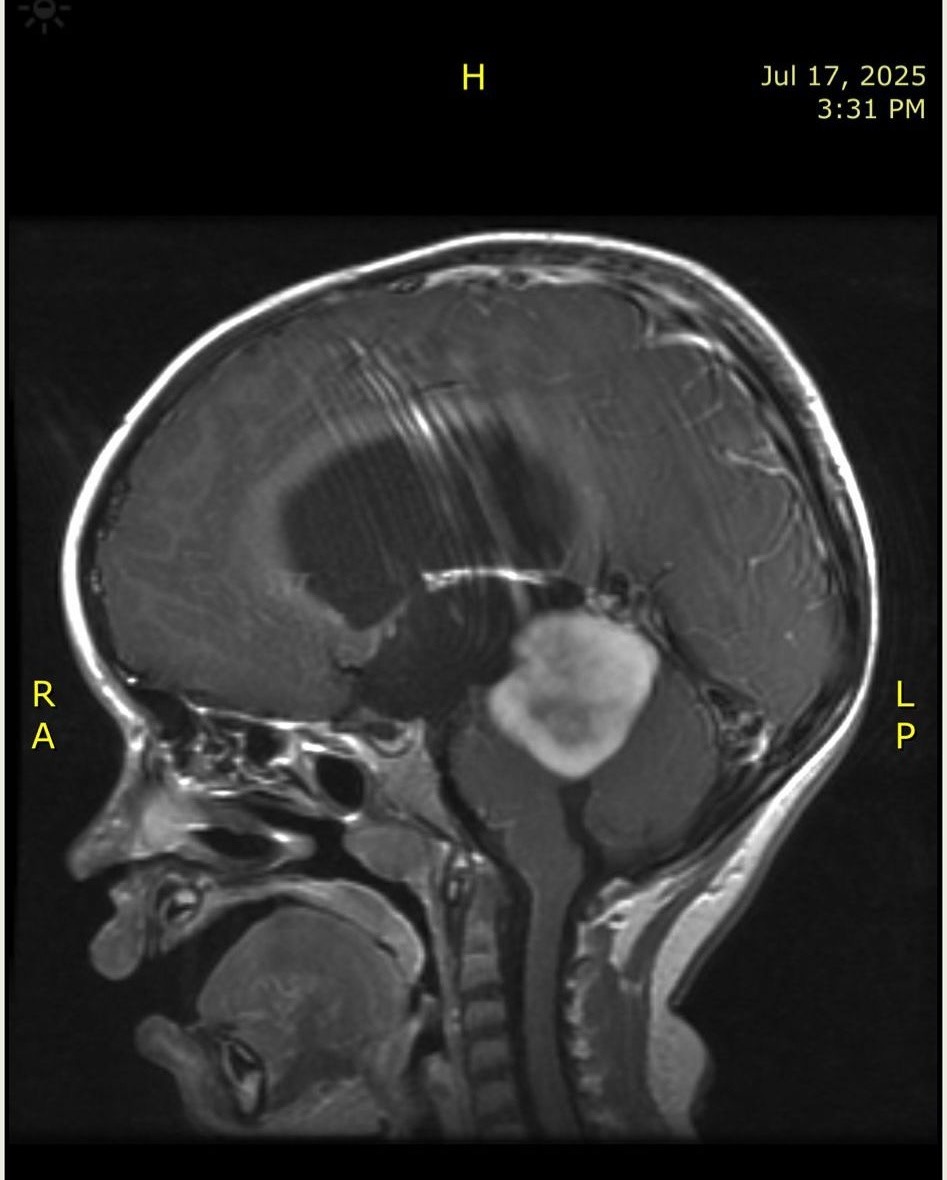

It all started with very strong headaches. My parents took me to the hospital, and that’s when they discovered I had a tumor in the center of my brain: a Pilocytic astrocytoma (a slow-growing, low-grade tumor), measuring 3 x 3.1 x 3.5 cm. That same day, I had to be airlifted by helicopter to a larger, specialized hospital because the tumor had caused a dangerous buildup of fluid in my head. There, I had my first emergency surgery.

My tumor cannot be surgically removed, and in my most recent MRI it had grown to 3.6 x 3.6 x 3.5 cm. Even though it can’t be taken out, it can be treated with medication and chemotherapy. This will be a long journey, and my parents need to take many days off work to be by my side. That means less income at home and more expenses for transportation, hospital visits, medicines, and daily care.